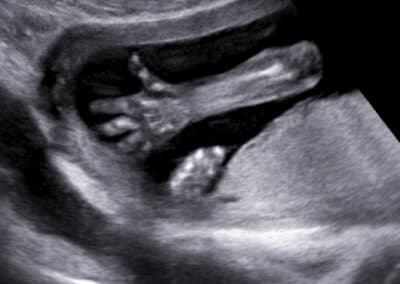

Vyšetření ručičky

Ultrazvukové vyšetření provádíme přes břišní stěnu. Močový měchýř maminky nemusí být naplněný, protože miminko již není v pánvi ale v dutině břišní. Určíme uložení a stav placenty, množství plodové vody a počet cév v pupečníku. Změříme příčný průměr a obvod hlavičky, obvod bříška, délku stehenní kosti a podrobně vyšetříme všechny orgány miminka. Pokud si budete přát znát pohlaví miminka, rádi vám jej sdělíme. Budete-li si chtít připojit 3D-4D ultrazvukové vyšetření s reálným zobrazením vzhledu miminka , připojíme jej. Při vyšetření se řídíme zásadami Fetal Medicine Foundation a všichni lékaři mají FMF certifikát na ultrazvukové vyšetření miminka ve 2. trimestru .